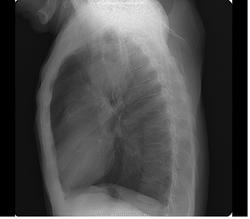

Не могу согласиться со всеми. Образование большое и, если был рак, то при таком размере контуры не должны быть такими чёткими и больше волнистыми, изменения окружающего ЛР нет. Характерное место для лимфом, но не встречал их распада. Абсцесс не надо ислючать, они уже не дают классической клинической картины. КТ, бронхоскопия, гистология.

А почему теперь абсцессы типичной клиники не дают? Мне представляется, что если бы был недренированный абсцесс такого размера, то мужчина бы себя очень плохо чувствовал, температурил и вообще помирал.... А то что контуры четкие - встречала в литературе, как некоторые авторы пытались соотнести рентгенологическую картину и гистологический тип опухоли.. так вот при каком-то виде рака указывали сохранение четких контуров образования даже при больших размерах

+1, однозначно- связь с плеврой, полость распада

Периферический с распадом.

Постараюсь отследить судьбу пациента. На данный момент его направили с заключением абсцесс верхней доли в стационар.

Верхний контур не такой уж четкий и ровный, тяжи к плевре.. внутренние контуры "полости" тоже.

Периферический, доросший до центрального с распадом.

все таки полость не такая щелевидный краевой распад.

Написано T4 N1 M1b NSCLC adenocarcinoma of lung